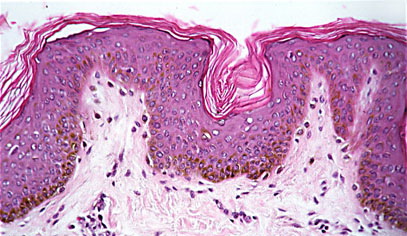

Atlas of skin histopathology

Thin Dark Skin = الجلد القاتم الرقيق